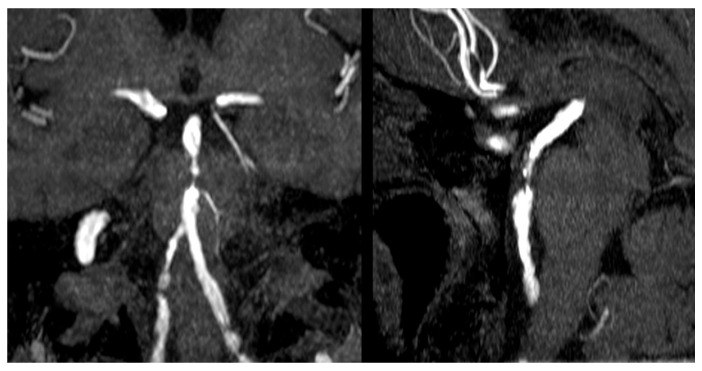

Abstract Image